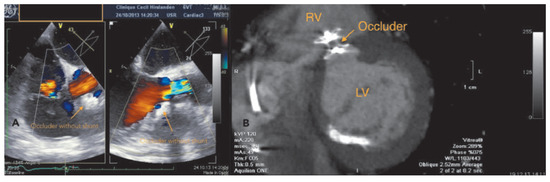

The fact that non-valvular (non-rheumatic) atrial fibrillation creates detectable thrombi in 17% of patients without oral anticoagulation and that 16% of the 17% (over 90% relatively) reside in the left atrial appendage (LAA), suggest that patients w...